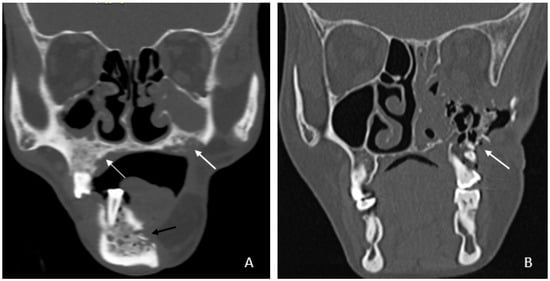

• Bone involvement: 18 patients had only mandibular ORN, while 16 had combined mandibular and maxillary involvement (Figure 1B). Isolated maxillary ORN was observed only once (Figure 1A). Bilateral maxillary involvement alone was not observed.

Figure 1. (A) Coronal CT image showing involvement of bilateral upper alveolus (white arrow) and mandible with areas of cortical erosion, trabecular thickening, and sclerosis (black arrow). (B) Coronal CT image showing extensive ORN of the left maxilla—seen as destruction and collapse (arrow).